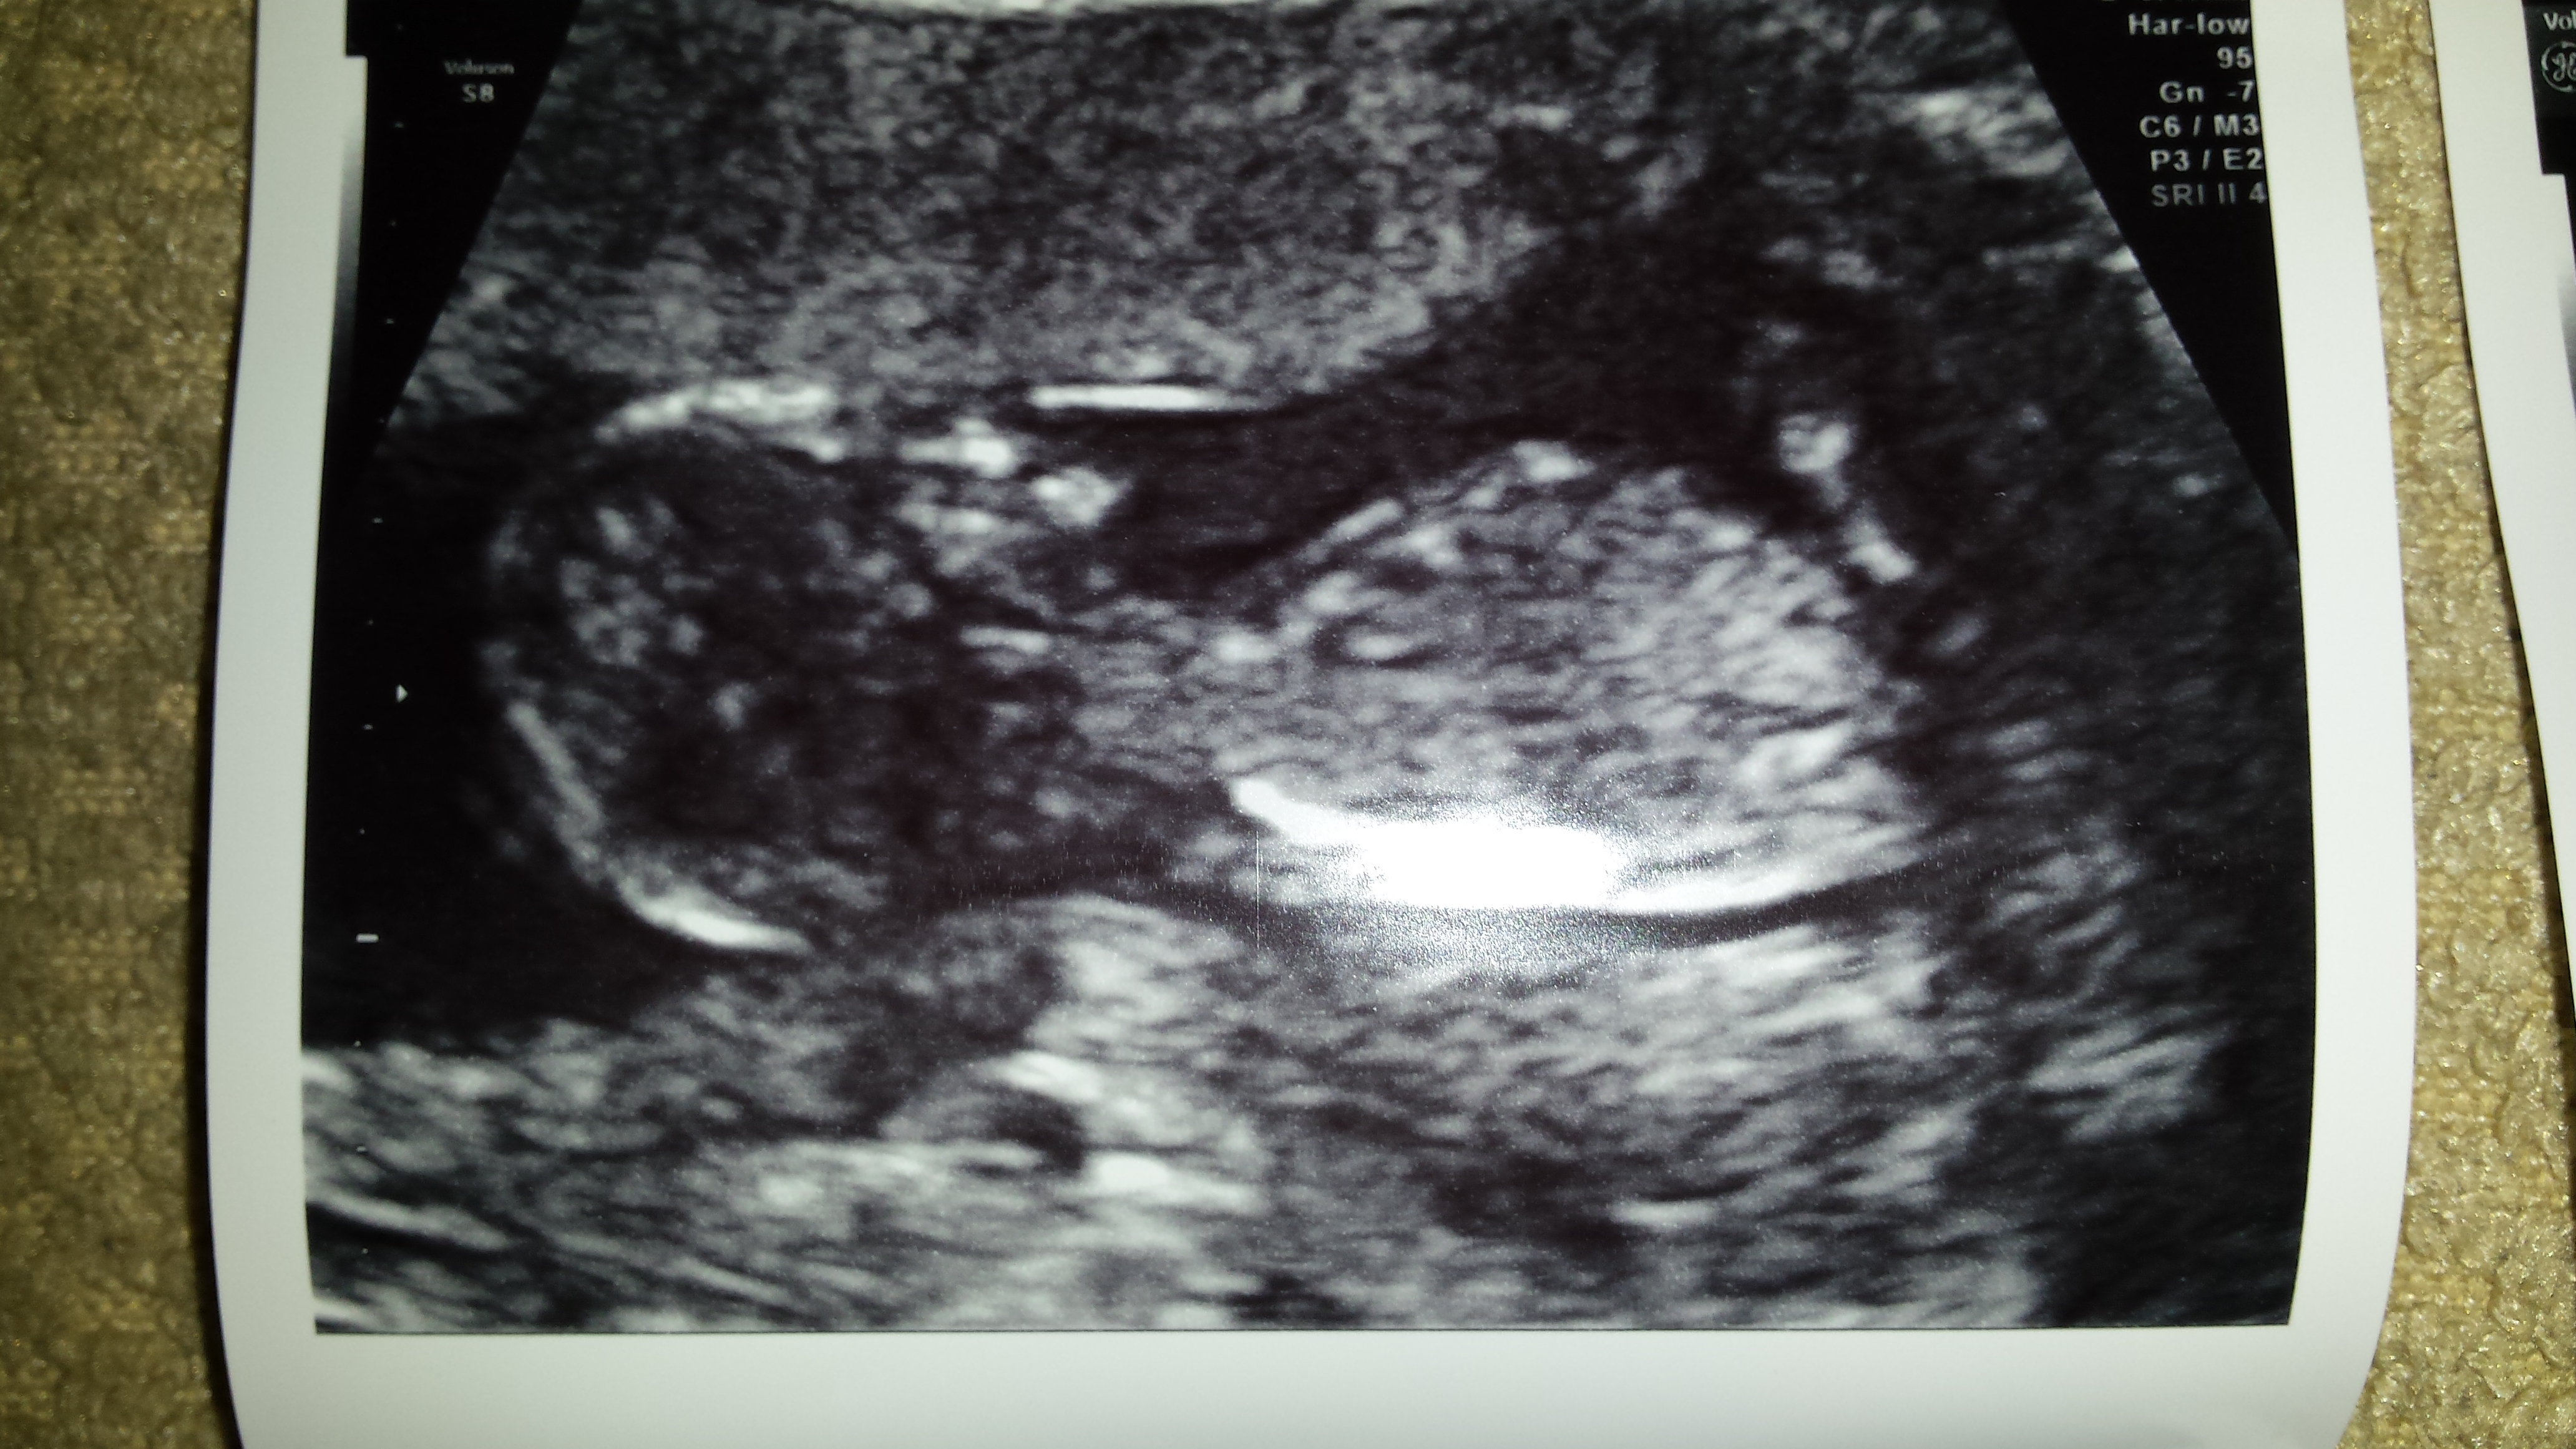

Nub might be cut off, but I lean boy.

Boy

I think boy too.